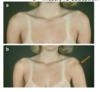

presentation of posterior dislocation

They present with an internally rotated and adducted arm. There is also squaring of the shoulder and a prominent coracoid process.

- light bulb sign